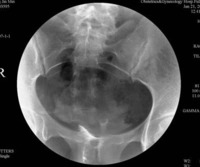

1、造影剂注入后显影良好、对比度满意。

2、子宫腔和/或输卵管显示清晰,诊断明确。

准确的摄影体位及位置,包括小骨盆上下左右边缘及感兴趣区的显示。复旦大学附属妇产科医院影像科张国福

(2)在透视下缓慢注入造影剂至宫腔和/或输卵管显示满意后摄片,必要时加摄斜位或其他位置片。

4、影像层次分明:盆腔层次分明,子宫腔和/或输卵管显示清晰。